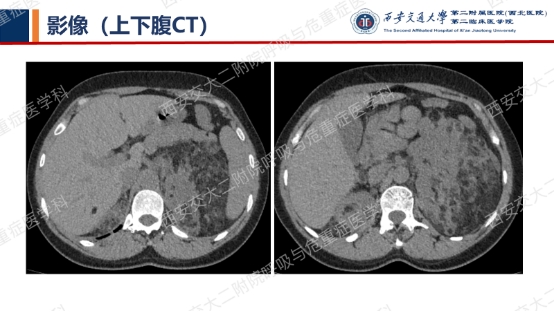

上图与Case 2比较相似,所以诊断LAM没有问题,还需进一步排查系散发型还是结节性硬化症累及。

影像学评估发现患者多系统受累(肝脏错构瘤、双肾血管平滑肌脂肪瘤、颅脑多发异常信号结节)。追问病史,患者本人无皮疹、癫痫及智力低下;患者儿子有面部皮脂腺瘤,无癫痫及智力低下,胸腹部CT未见异常,皮肤科已确诊结节性硬化症;患者女儿面容及智力均正常;建议患者进一步行TSC基因检测,结果回报TSC2突变,结节性硬化症诊断明确。

患者尝试口服西罗莫司2mg/日,消化道难以耐受,减至1mg/日,仍有恶心等不适,自行停药,不愿再尝试药物治疗,目前随访观察中。